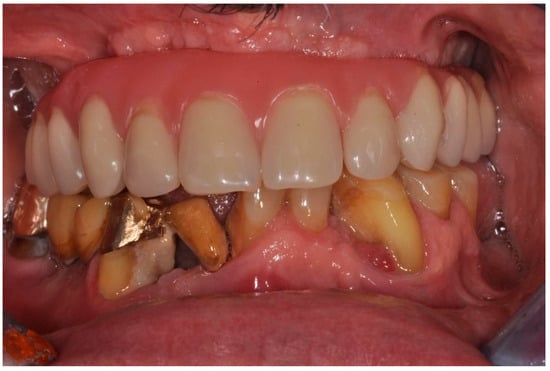

| Flanagan D. et al. [23] | J Oral Implantol | 2015 | clinical and radiographic: full-mouth radiographic series, panoramic and a bimaxillary cone beam computerized scan and mounted study casts | -One patient | Subject of 34 yo male; severely carious teeth and associated chronic abscesses (kidney transplant delayed) Comorbidities: IgA nephropathy, tabagism, hypertension and secondary hyperparathyroidism. Hemodialysis three times weekly. Ph. Therapy: Nephrocaps vitamin (B) supplement, amlodepine, besylate, cinacalcet, metoprolol, paroxetine. Bilateral compound ulnar and radial fractures, 2 blood transfusions. | Successfully treated with dental implant-supported fixed prostheses: fixed bimaxillary porcelain fused to metal implant-supported complete dentures |

| Flanagan D. et al. [23] | J Oral Implantol | 2015 | -Implant treatment for patients with IgA nephropathy (secondary hyperparathyroidism and osteodystrophy) may be successful. -Appropriate calcium therapy is important serum calcium to prevent inappropriate bone remodeling | 2 years | Long-term dialysis patient with end-stage renal disease (ESRD)also referred to as chronic kidney disease (CKD) due to IgA nephropathy complicated by severe secondary hyperparathyroidism and renal osteodystrophy | |